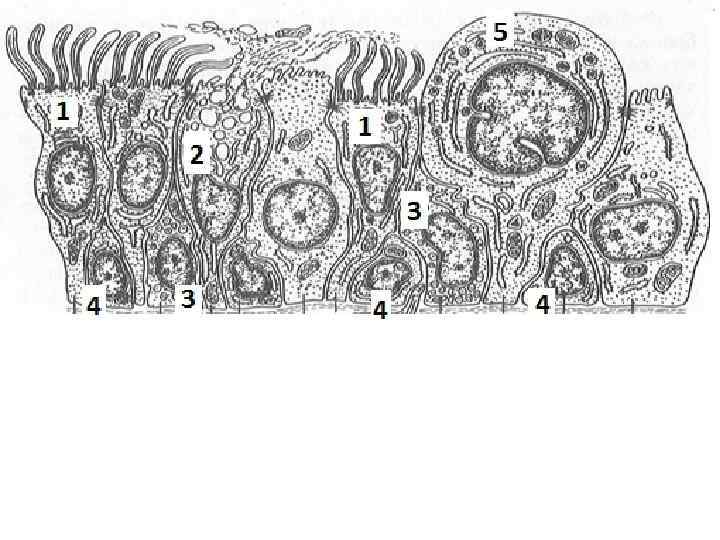

Эпителий трахеи содержит реснитчатые, бокаловидные, вставочные и эндокринные клетки. Реснитчатые клетки имеют реснички, колеблющиеся против движения вдыхаемого воздуха. Они удаляют микроорганизмы и инородные частицы. Бокаловидные клетки секретируют муцины - слизь, которая склеивает инородные тела, бактерии и облегчает их выделение. Микроворсинчатые клетки являются хеморецепторными. Базальные или вставочные клетки играют роль камбия.

Бокаловидные реснитчатые клетки образуют слизисто-реснитчатый (мукоцилиарный) конвейер. В норме соотношение бокаловидных и реснитчатых клеток равно 1/10. В этом случае осуществляется оптимально работа конвейера: реснички успевают эвакуировать всю слизь, образованную бокаловидными клетками. При курении, воспалении трахеи соотношение изменяется в пользу бокаловидных клеток. Образуется избыток слизи, который не успевает удаляться, теряет свои бактерицидные свойства и инфицируется, формируется трахеит курильщика.